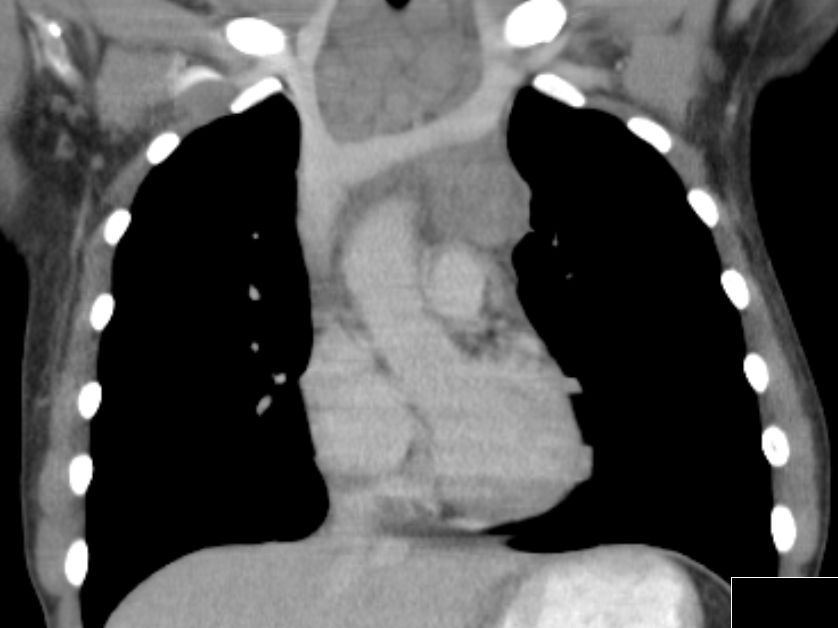

| Mediastinum | 30-jährige Frau therapieresistentem Husten. Das Röntgenbild zeigt eine Verbreiterung des oberen Mediastinums. Bronchoskopisch Impression der Trachea. Mediastinoskopische Biopsie: EBV-negatives klassisches Hodgkin-Lymphom. | ||